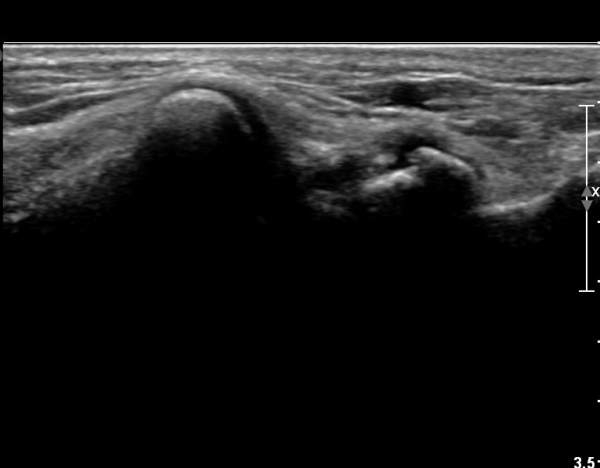

ŽÃËÀÚ¸¦ Á¶±Ù ³»ÃøÀ¸·Î À̵¿ÇÏ´Ï »ï°¢°ñ Ç¥Ãþ¿¡¼­ °íÆíÀÌ °üÂûµµ´Ï´Ù(»çÁø 2).